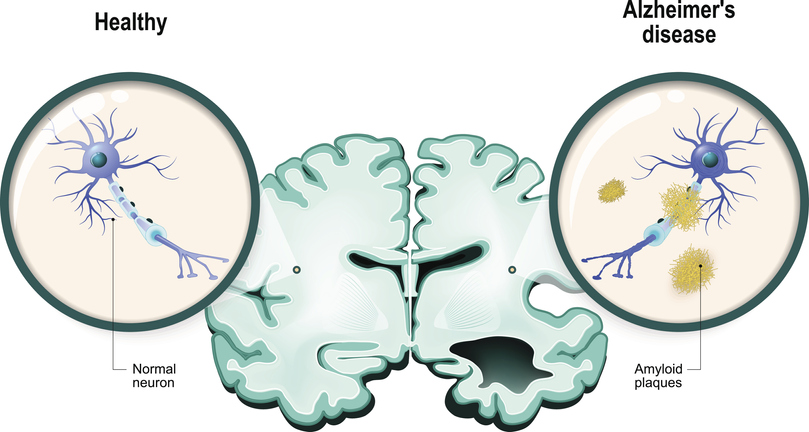

Αυτό που είδε στο μικροσκόπιο ήταν εμφανείς διαφορές στον ιστό του εγκεφάλου σε μορφή λανθασμένα αναδιπλουμένων πρωτεϊνών και νευροϊνιδιακών νημάτων.

Αυτές οι πλάκες και τα νήματα λειτουργούν μαζί ούτως ώστε να σπάσουν τη δομή του εγκεφάλου.

Οι πλάκες προκύπτουν όταν μια άλλη πρωτεΐνη στην λιπώδη μεμβράνη γύρω από τα νευρικά κύτταρα αποκόπτεται από ένα συγκεκριμένο ένζυμο, καταλήγοντας σε βήτα-αμυλοειδεις πρωτεΐνες, οι οποίες είναι κολλώδεις και τείνουν να συγκολλώνται όλες μαζί.

Η συγκέντρωση αυτή δημιουργεί αυτά που ονομάζουμε πλάκες.

Οι πλάκες μπλοκάρουν την μετάδοση σημάτων, άρα και την επικοινωνία μεταξύ των κυττάρων.

Επίσης φαίνεται να προκαλούν ανοσοποιητικές αντιδράσεις που προκαλούν την καταστροφή των αλλοιωμένων νευρικών κυττάρων.